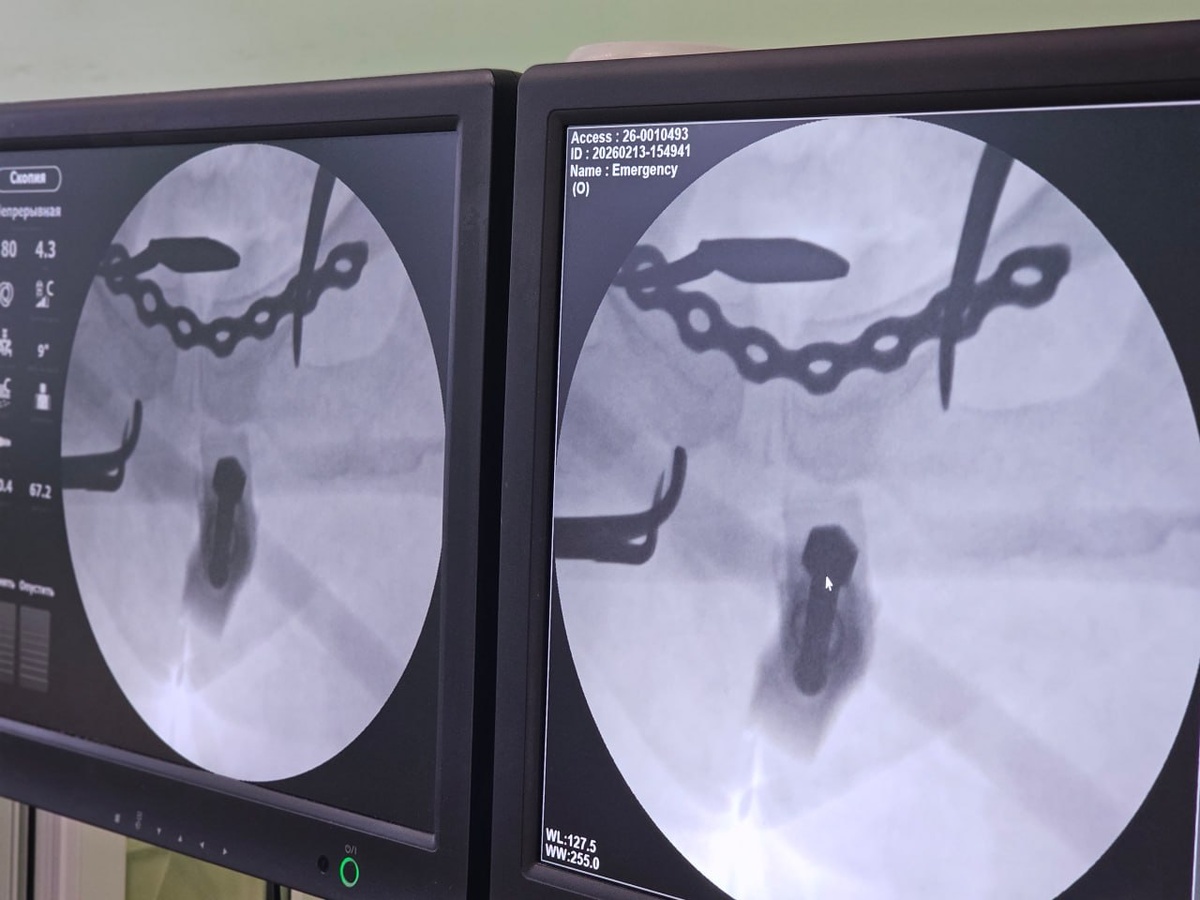

41-летняя женщина в январе упала с «ватрушки» на большой скорости и переломала себе таз. Медики из БСМП №1, куда попала пациентка, поставили крайне тяжёлый диагноз: перелом боковых масс крестца с двух сторон и разрыв лонного сочленения (вертикального соединения верхних ветвей лобковых костей).

Как рассказали в пресс-службе регионального Минздрава, Помощь женщине оказывали с помощью нового аппарата для внешней фиксации переломов, который позволяет выполнить стабилизацию максимально быстро и малоинвазивно.

Местной жительнице помощь оказывали в два этапа. Как только она поступила в больницу, ей провели закрытую репозицию перелома костей таза (процедуру, направленную на восстановление нормального анатомического положения костных отломков) со стабилизацией аппаратом внешней фиксации. Вся операция заняла всего 20 минут.

На втором этапе – после тщательного обследования и предоперационного планирования – пациентке окончательно зафиксировали переломы специализированными металлоконструкциями – винтами и титановой пластиной.